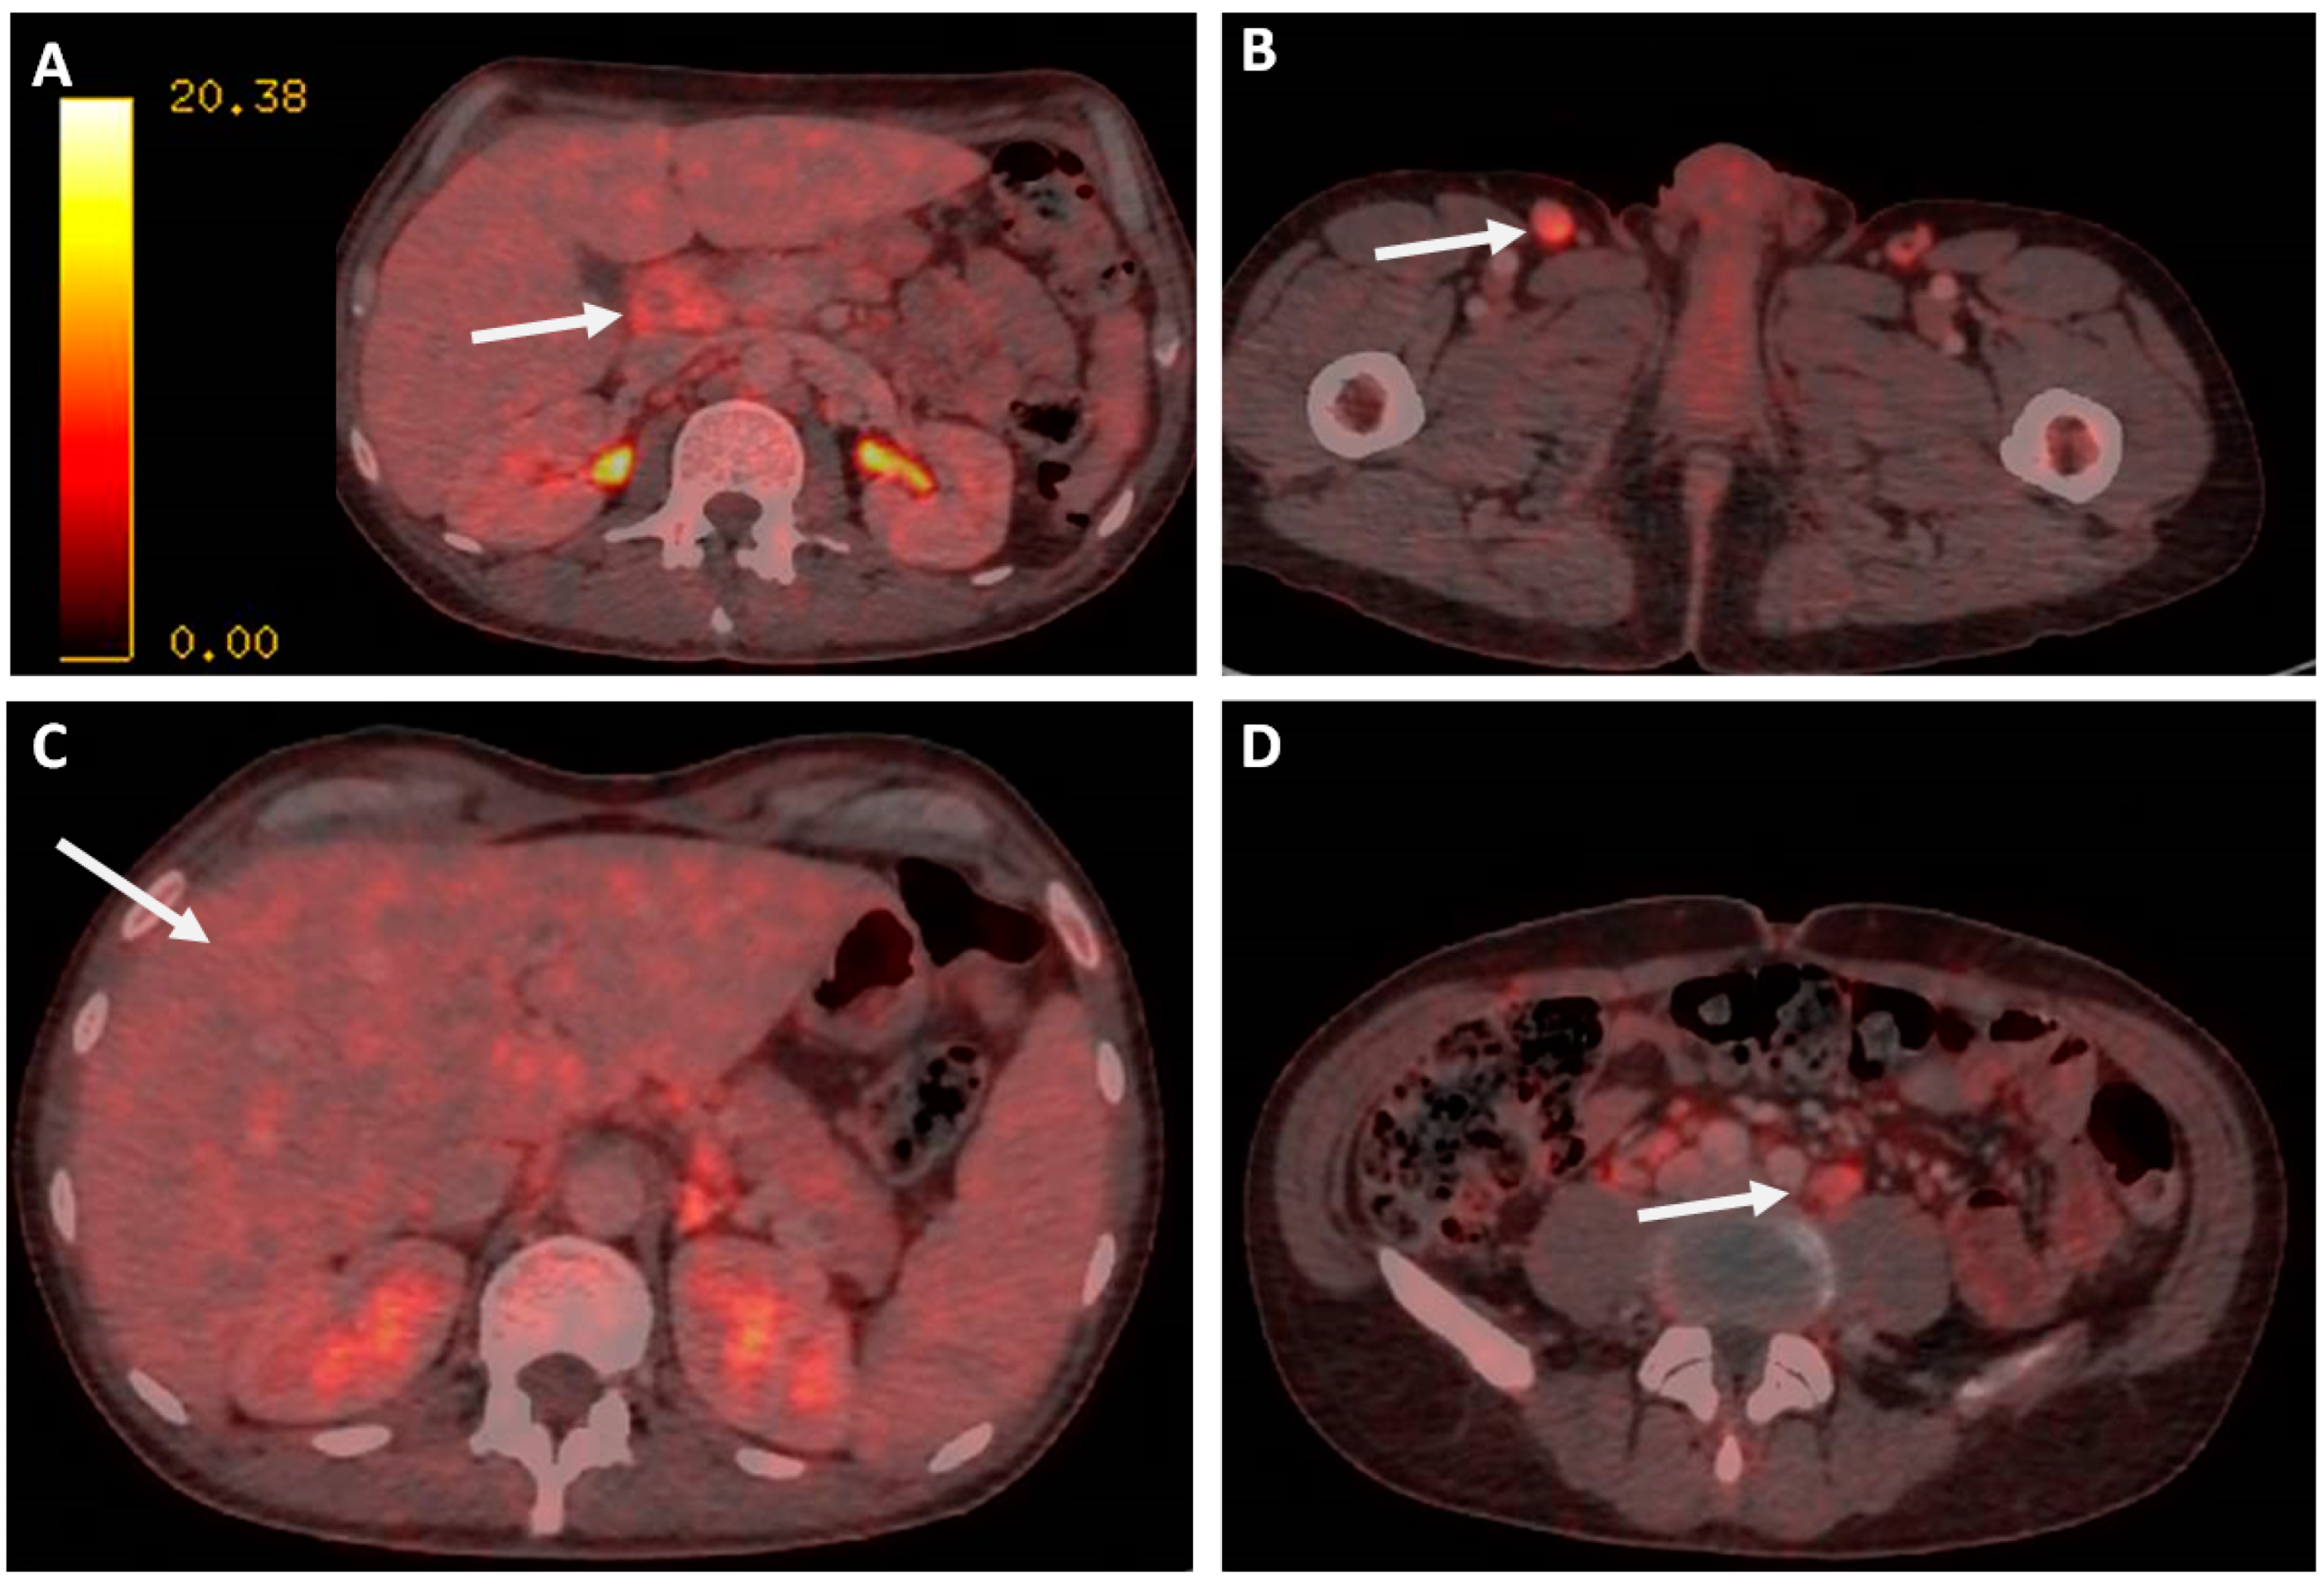

In order to confirm and stage the disease, a positron emission tomography CT (PET-CT) scan was requested, revealing multiple supradiafragmatic and infradiafragmatic adenopathies, most of them with discrete–moderate fluorodeoxyglucose (FDG) uptake (some with intense activity). The one at the right inguinal region was the most accessible for biopsy (Figure 2).

In addition, FDG uptake was revealed in the gastric fundus, showing only data of gastritis, hepatomegaly without significant alterations to the metabolism, and a discrete diffuse hypermetabolism in BM. No alterations were found in the rest of the study.

Figure 2. PET-CT scan images. (A): The hepatic hilum lymphadenopathy is marked with arrows. (B): Inguinal lymphadenopathy. (C): Hepatomegaly. (D) Mesenteric lymphadenopathy.